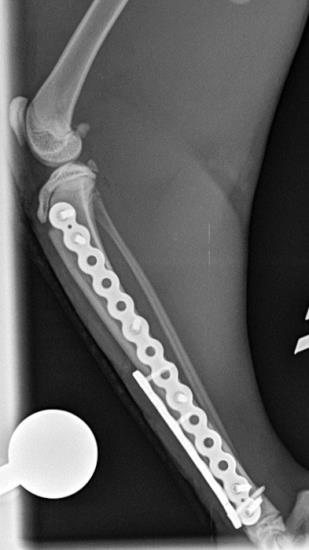

These radiographs show a distal tibial fracture in a six-month cat. Multiple fissure lines can be seen extending towards the distal tibial physis. The tibia is a common site of non-union in the cat and plate failure by bending following tibial fracture stabilisation is reported. In this case, an orthogonal plate has been applied to the cranial aspect of the tibia. This not only allows increased construct stiffness in the sagittal plane but provides for an additional screw fixation point. This can be very useful with distal fractures.

The cat, in this case, was allowed early ambulation and went on to make a full recovery. The PAX advanced locking system is well suited to cat fracture repairs such as this.